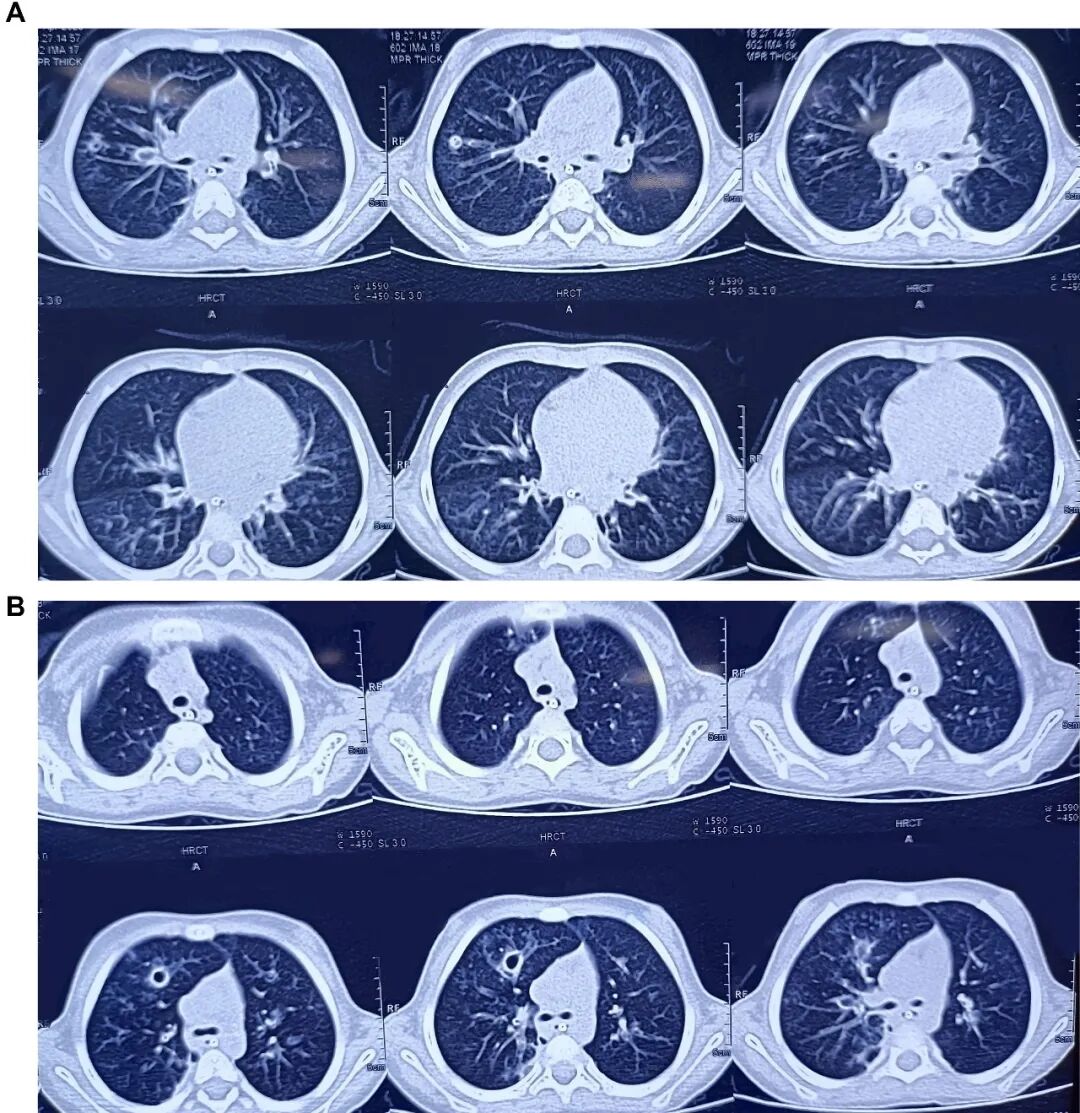

胸片显示双肺野过度充气,伴右肺中野不均匀浸润影及支气管壁增厚(图1)。胸部高分辨率CT扫描显示右肺上叶前段可见厚壁囊腔,可能存在交通,紧邻管壁明显增厚的亚段支气管——提示囊性支气管扩张(图2)。免疫功能缺陷检查已排除:HIV报告正常,免疫球蛋白谱正常,淋巴细胞亚群分析正常。IgA=54.67 mg/dL,IgG=990.32 mg/dL,IgM=404.186 mg/dL,IgE=16.3 IU/mL,CD3(T细胞)=2237.32 个/μL ,62.85% ;CD4 TH细胞=1165.21 个/μL ,32.73% ;CD8 T细胞=1065.26 个/μL,29.92%;CD4/CD8比值1.09,均处于正常范围

1.患者入院时胸片。显示双肺野过度充气,左肺中野不均匀密度增高影伴支气管周围增厚。

图2.A,胸部高分辨率CT扫描显示左右肺囊性支气管扩张,伴有空穴病变。B,胸部高分辨率CT扫描显示右肺上叶前段有厚壁囊性腔体,并有囊性支气管扩张的证据。

临床上,这种情况属于小气道疾病,其特征是呼吸急促、啰音、喘息和低氧血症,症状出现后持续很长时间,如本例患者所示。持续性湿咳和喘息是最常见的症状。胸部CT显示肺不张、支气管周围增厚、空气潴留以及伴有马赛克征的支气管扩张,这使得感染后闭塞性细支气管炎成为该患者重要的鉴别诊断。关于Liddle综合征肺部表型的数据很少,儿科病例也稀少。